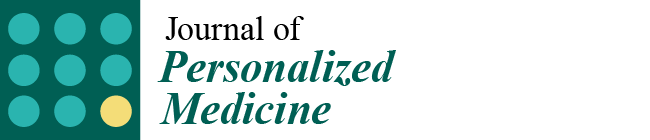

1.1. Classification of Cardiomyopathies from a Traditional Viewpoint to a Personalized Approach

1.2. Sudden Cardiac Death Risk in Cardiomyopathies: From a Traditional Viewpoint to a Personalized Approach